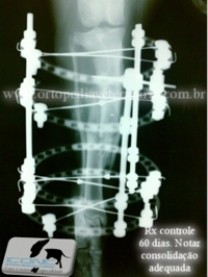

Fratura cominutiva de tíbia em Labrador. Colocação de Fixador Circular em abordagem fechada, permite apoio precoce com o mínimo dano adicional oa tecido ósseo.